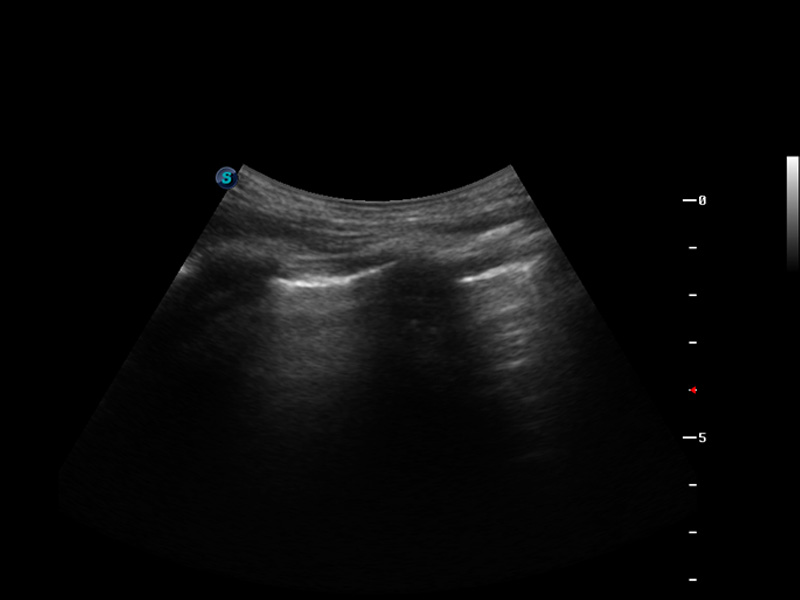

S9便携式彩色多普勒超声诊断仪是球速体育入口研发的高端便携彩超设备,外观设计新颖、产品性能卓越。S9在便携超声领域采用了突破传统的触摸屏交互设计,并以先进的软件硬件技术和设计理念,为您带来清晰的图像质量、稳定的工作性能和便捷的操作体验。

成像技术

μ-Scan微米成像